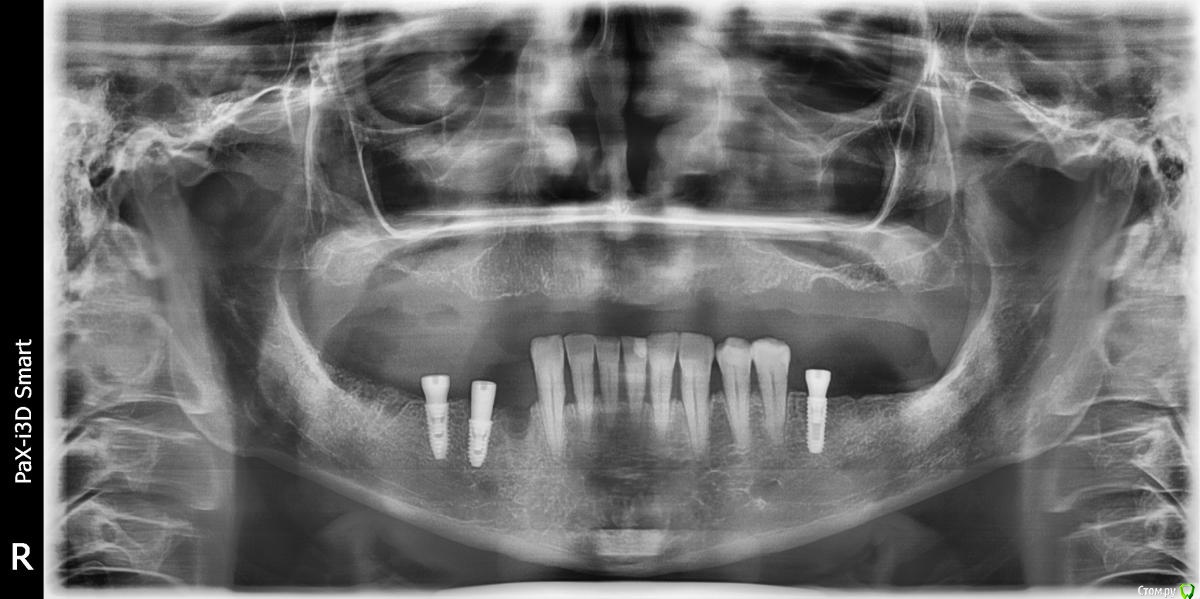

kamranchick Опубликовано 2 февраля, 2018 Поделиться Опубликовано 2 февраля, 2018 Подошла пациентка через год после установки ФДМ.определяется выделяемое возле крестального модуля. можно ли вопрос решить местно? мед чистка хлорегексидин перекись ССТ с бугра вестибулярнолибо на удаление имплантата?В связи с последними тендециями, вроде все стараются оставить имплантаты, изменились ли у Вас взгляды? Ссылка на комментарий

TIGER Опубликовано 5 февраля, 2018 Поделиться Опубликовано 5 февраля, 2018 Подошла пациентка через год после установки ФДМ.определяется выделяемое возле крестального модуля. можно ли вопрос решить местно? мед чистка хлорегексидин перекись ССТ с бугра вестибулярнолибо на удаление имплантата?В связи с последними тендециями, вроде все стараются оставить имплантаты, изменились ли у Вас взгляды?явный периимплантит с чем связываете?откроетесь,будет на половину....в грануляциях,кость не наростёт к сожалению Ссылка на комментарий

kamranchick Опубликовано 6 февраля, 2018 Автор Поделиться Опубликовано 6 февраля, 2018 явный периимплантит с чем связываете?откроетесь,будет на половину....в грануляциях,кость не наростёт к сожалениюя вообще не знаю, ну единственное что с чем могу связывать, на кт в этом месте был пломбировочный материал в кости, какой нибудь йодоформ, ну только с этим могу связывать Ссылка на комментарий

kamranchick Опубликовано 6 февраля, 2018 Автор Поделиться Опубликовано 6 февраля, 2018 Снять формик. Прозондировать. Определить вид дефекта и прогноз. Дальше либо имплантопластика, либо "навынос" и реимплантация.была бы одиночка можно было и не париться, но везде имплантатики стоят, получается если на вынос то еще + 6 месяцев Ссылка на комментарий

kamranchick Опубликовано 9 февраля, 2018 Автор Поделиться Опубликовано 9 февраля, 2018 сверху сьемник так что вариантик с консолькой мне понравился, сегодня воткну.интересно, контамирована поверхность имплантата, и только костное ложе в области 4.4? в области 4.5 все ли будет пучком?) и почему все таки тут он возник этот периимпл? Ссылка на комментарий

kamranchick Опубликовано 9 февраля, 2018 Автор Поделиться Опубликовано 9 февраля, 2018 (изменено) после операции нашел снимок Изменено 9 февраля, 2018 пользователем kamranchick Ссылка на комментарий

dzhancha Опубликовано 10 февраля, 2018 Поделиться Опубликовано 10 февраля, 2018 сверху сьемник так что вариантик с консолькой мне понравился, сегодня воткну.интересно, контамирована поверхность имплантата, и только костное ложе в области 4.4? в области 4.5 все ли будет пучком?) и почему все таки тут он возник этот периимпл?Замечательный ретенционной пункт для зубного налета и бактерий + отсутствие нагрузки. Недавно была пациентка, имплантат без фдм, явилась через 2 года после установки. Убыль кости на 3 витка, также кратером. Ссылка на комментарий